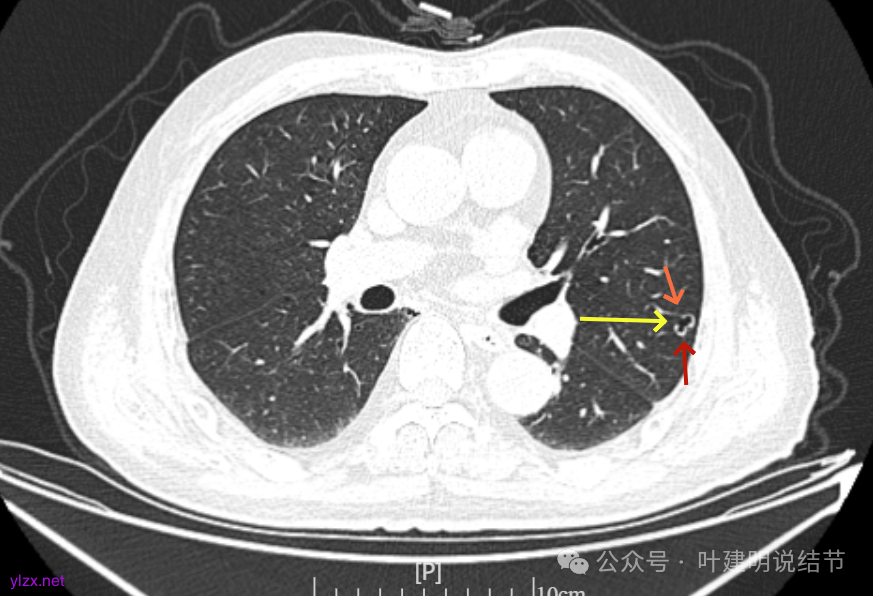

再看2023年时的影像主要层面:

左上当时也有,但囊壁明显是较现在薄的。

左肺上叶红色这处是囊腔型病灶,囊壁略不均,似有微小血管进入囊壁,对比2023年4月整个囊腔来讲有扩大,需要考虑囊腔型肺癌的可能性大。右侧蓝色的并不是典型囊腔型肺癌的表现,再加上两肺绿色这些慢支肺气肿与肺大泡的影像,右侧的就更加不确切,至少近期不能够考虑右侧也要开刀的事情。其实左侧的主病灶相对于其他表现更典型的囊腔型肺癌来说,由于囊壁密度偏高,也不是百分百必定是肺癌。我的想法还是先等脑梗情况稳定,并且间隔4~6个月复查病灶再有进展在考虑单孔胸腔镜下局部切除就可以。淋巴结可以考虑采样,但一般不至于阳性。破是不会切破的。消融不建议,囊腔灶更难通过穿刺获得病理依据,况且东西在边上,能局部楔切,当然首选手术。意见供参考!